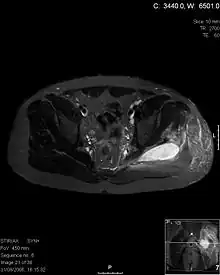

Transverse T2 magnetic resonance imaging section through the hip region showing abscess collection in a patient with pyomyositis.

Diagnostic methodDiagnostic method used for PM includes ultrasound, CT scan and MRI. Ultrasound can be helpful in showing muscular heterogeneity or a purulent collection but it is not useful during the first stage of the disease. CT scan can confirm the diagnosis before abscesses occur with enlargement of the involved muscles and hypodensity when abscess is present, terogenous attenuation and fluid collection with rim enhancement can be found. MRI is useful to assess PM and determine its localization and extension